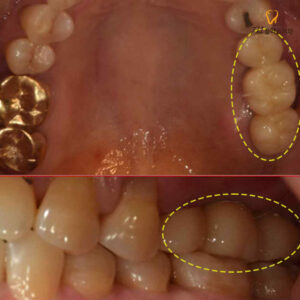

대현동치과 환자 치료전 사진

위 환자분은 50대 여성분으로,

음식물을 저작할 때마다 왼쪽편이 불편하여

내원해 주셨는데요.

특히 보철물 사이로 음식물도 많이 끼고,

흔들리는 느낌이 있어 손으로 만져보았더니

흔들림도 있는 상태라 하셨습니다.

정밀한 진단을 위해

파노라마 촬영을 진행해 보았더니

금으로 수복된 대구치 중

앞쪽 치아의 뿌리 쪽으로

염증이 발생하여 있었으며,

염증이 퍼져 앞 치아와 뒤쪽 치아까지

치조골이 소실된 상태였습니다.

이미 염증이 심하게 번진 상태라

보존하기 어려워 3개의 치아 모두

발치를 진행한 후 대현동치과 임플란트를

식립하기로 하였습니다.